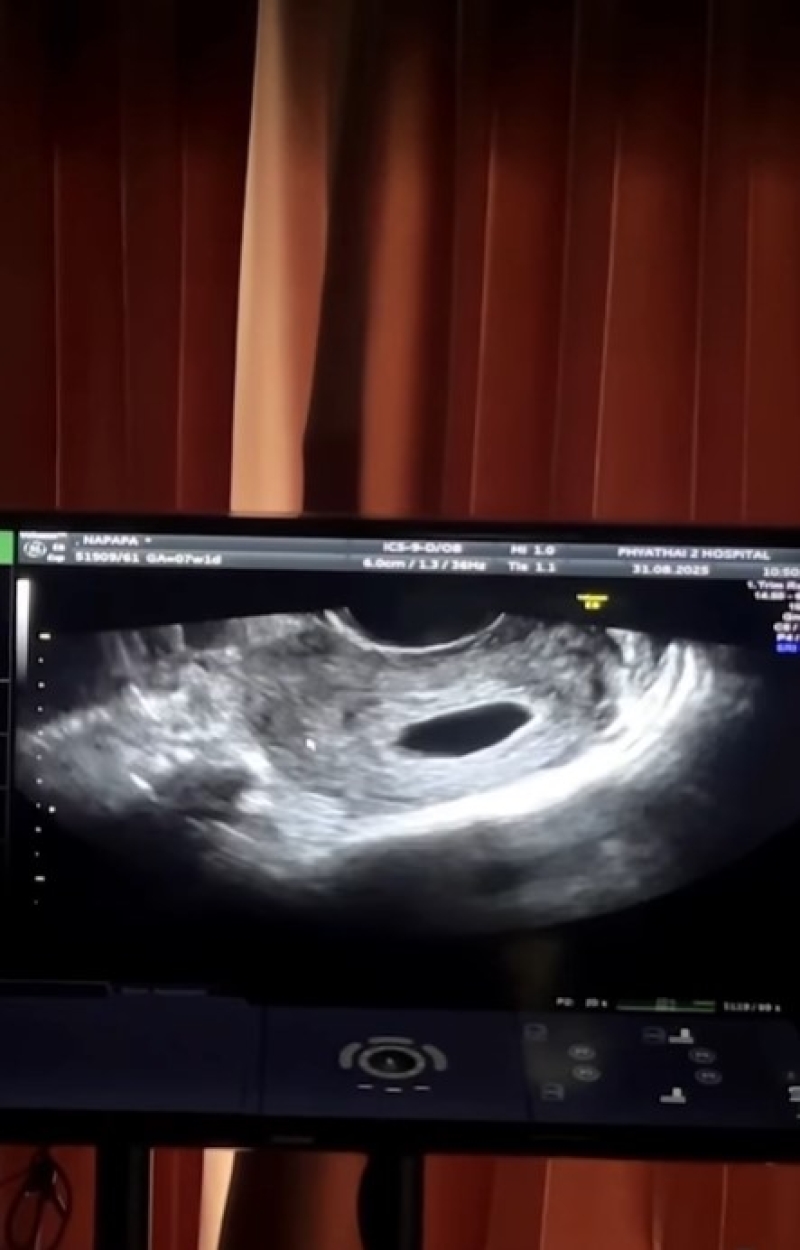

เรียกได้ว่า เป็นอีกหนึ่งบ้านที่แหนๆรอลุ้นเบบี๋อีกคน อย่าง แพท ณปภา และสามี พี ชานนท์ ที่กำลังจะมีน้องให้น้องให้ เรซซิ่ง ลูกชายคนแรก ซึ่งแฟนๆก็ต่างรอลุ้นว่าน้องจะมาตอนไหนนะ ล่าสุด แพท ได้ออกมาเผยข่าวดี เซอร์ไพรส์วันเกิดสามี โดยได้ตรวจขึ้น 2 ขีดนั้นเอง แต่แล้วโชคชะดาก็เล่นตลก เมื่อไปพบคุณหมอ แต่กับพบว่า ท้องลม นั้นเอง โดยแพทได้ใส่แคปชั่นสั้นๆว่า คือ …เรื่องมีอยู่ว่า

ภาพจาก pat_napapa